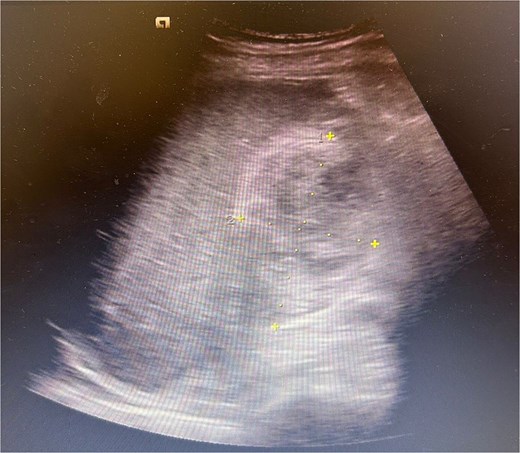

Ultrasound abdomen showed oedematous gallbladder with a heterogenous hypoechoic collection in gallbladder fossa (approximately measuring 9 × 4 cm) (Fig. 1). Acute haemorrhagic cholecystitis and intrahepatic gallbladder perforation was confirmed with magnetic resonance cholangiopancreatography and CT angio abdomen (small contrast blush in gallbladder lumen).

Ultrasound abdomen showing oedematous gallbladder with a heterogenous hypoechoic collection in gallbladder fossa (approximately measuring 9 × 4 cm).